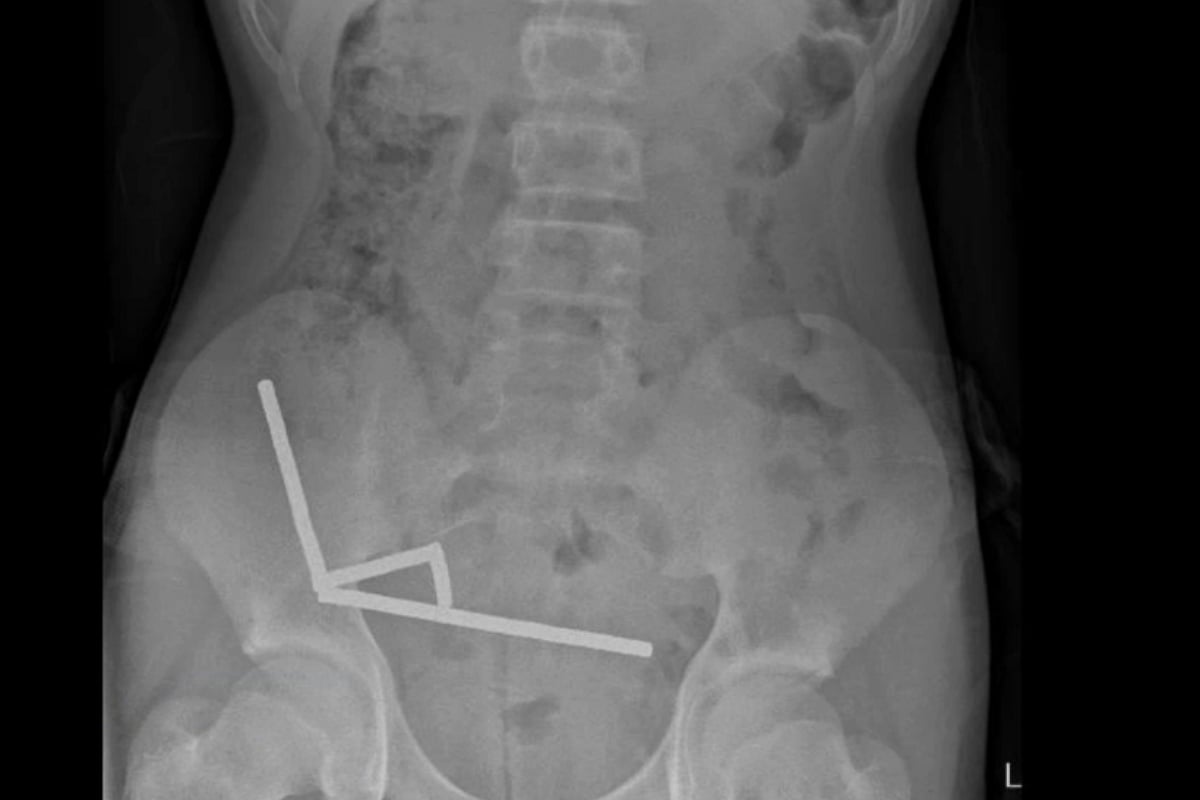

Teen Loses Part of Bowel After Swallowing 80+ Magnets

TUESDAY, Oct. 28, 2025 A young boy in New Zealand needed emergency surgery and lost part of his bowel after swallowing more than 80 small, high-powered magnets,